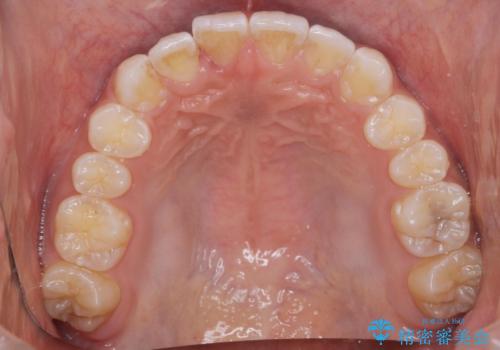

前歯のがたつき 1年かからず治療 マウスピース矯正

- 前歯のがたつきを主訴に来院。

インビザラインで歯を抜かずに並べました。

マウスピースの延長(リファインメント)もなく、短期間で綺麗に並びました。